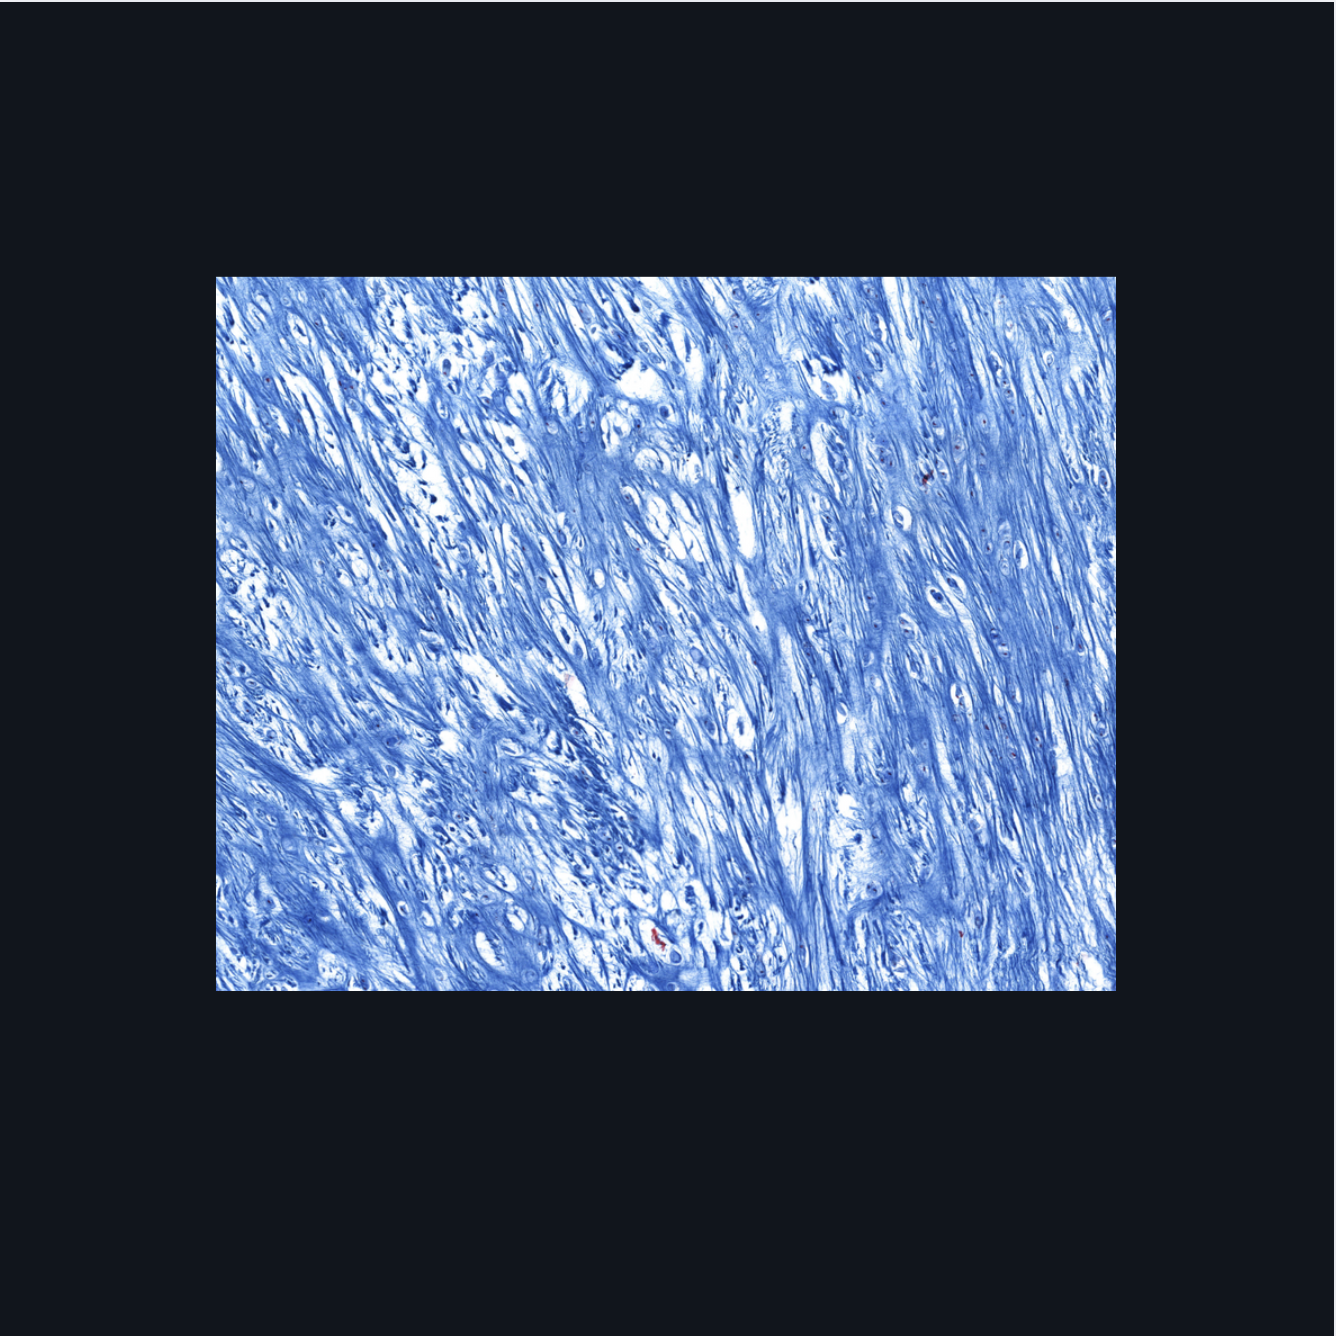

Fibrocartilage; intervertebral disc, articular disc, glenoid and acetabular labra

What type of cartilage is in the image? Where is this specific type of cartilage found?

Collagen fibers

This type of cartilage is abundant in what fibers?

Dense regular connective tissue; chondrocytes; lacunae

This cartilage is commonly mistaken as _____. However, when examined closely, _____are contained in _____ (identify pointed structures), making it a cartilage.